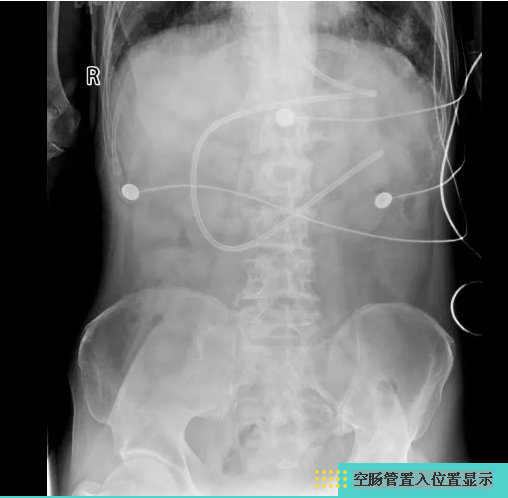

任冬飞医师在床旁为患者进行电子胃镜引导下空肠管置入术,引流出胃内容物并给予空肠营养支持

经过床旁X线检查,发现肺炎范围进一步扩大,更麻烦的是声门旁梨状窝处可见异物及气管内可见大量反流食物。专家会诊后,再次调整治疗方案:禁食水、给予空肠营养支持、应用液体管理、利尿及纠正休克等综合治疗急性肾衰,快速控制原发灶感染,患者的血小板终于有所回升。